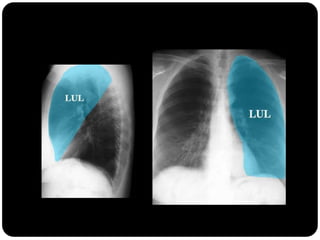

Pulmões – lobos - fissuras

 Direito: 3 lobos (fissura oblíqua = maior e a horizontal =

menor)

 Esquerdo : 2 lobos (fissura oblíqua)

 Pulmão direito:

 LSD: anterior, apical e posterior;

 LM: medial e lateral;

 LID: superior, basal medial, basal lateral,

basal anterior, basal posterior;

 Pulmão esquerdo:

 LSE: apicoposterior, anterior,

superior(língula), inferior(língula);

 LIE: segmento superior, basal antero-

medial, basal lateral e basal posterior;